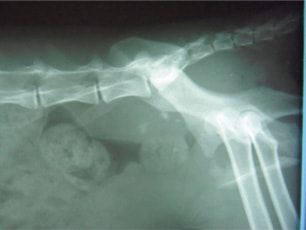

症例:交通事故による椎体脱臼

柴犬:9歳、避妊雌

交通事故直後、胸腰部に激しい疼痛、両後肢に完全麻痺を認め、シェフシェリントン徴候を呈していました。レントゲン検査において、第11-12胸椎間の脱臼が認められました。

脊髄の減圧、脊柱管の再構築・安定化を目的に、片側椎弓切除術およびMatrixMANDIBLE Plateによる椎体固定を実施しました。

隣接椎体を架橋するようにプレートを設置しました。

術後レントゲン写真

※当院にはMatrixMANDIBLE Plate以外のロッキングプレートシステムもいくつか用意があり、症例の性格や活動性、骨折部位によって使い分けています。